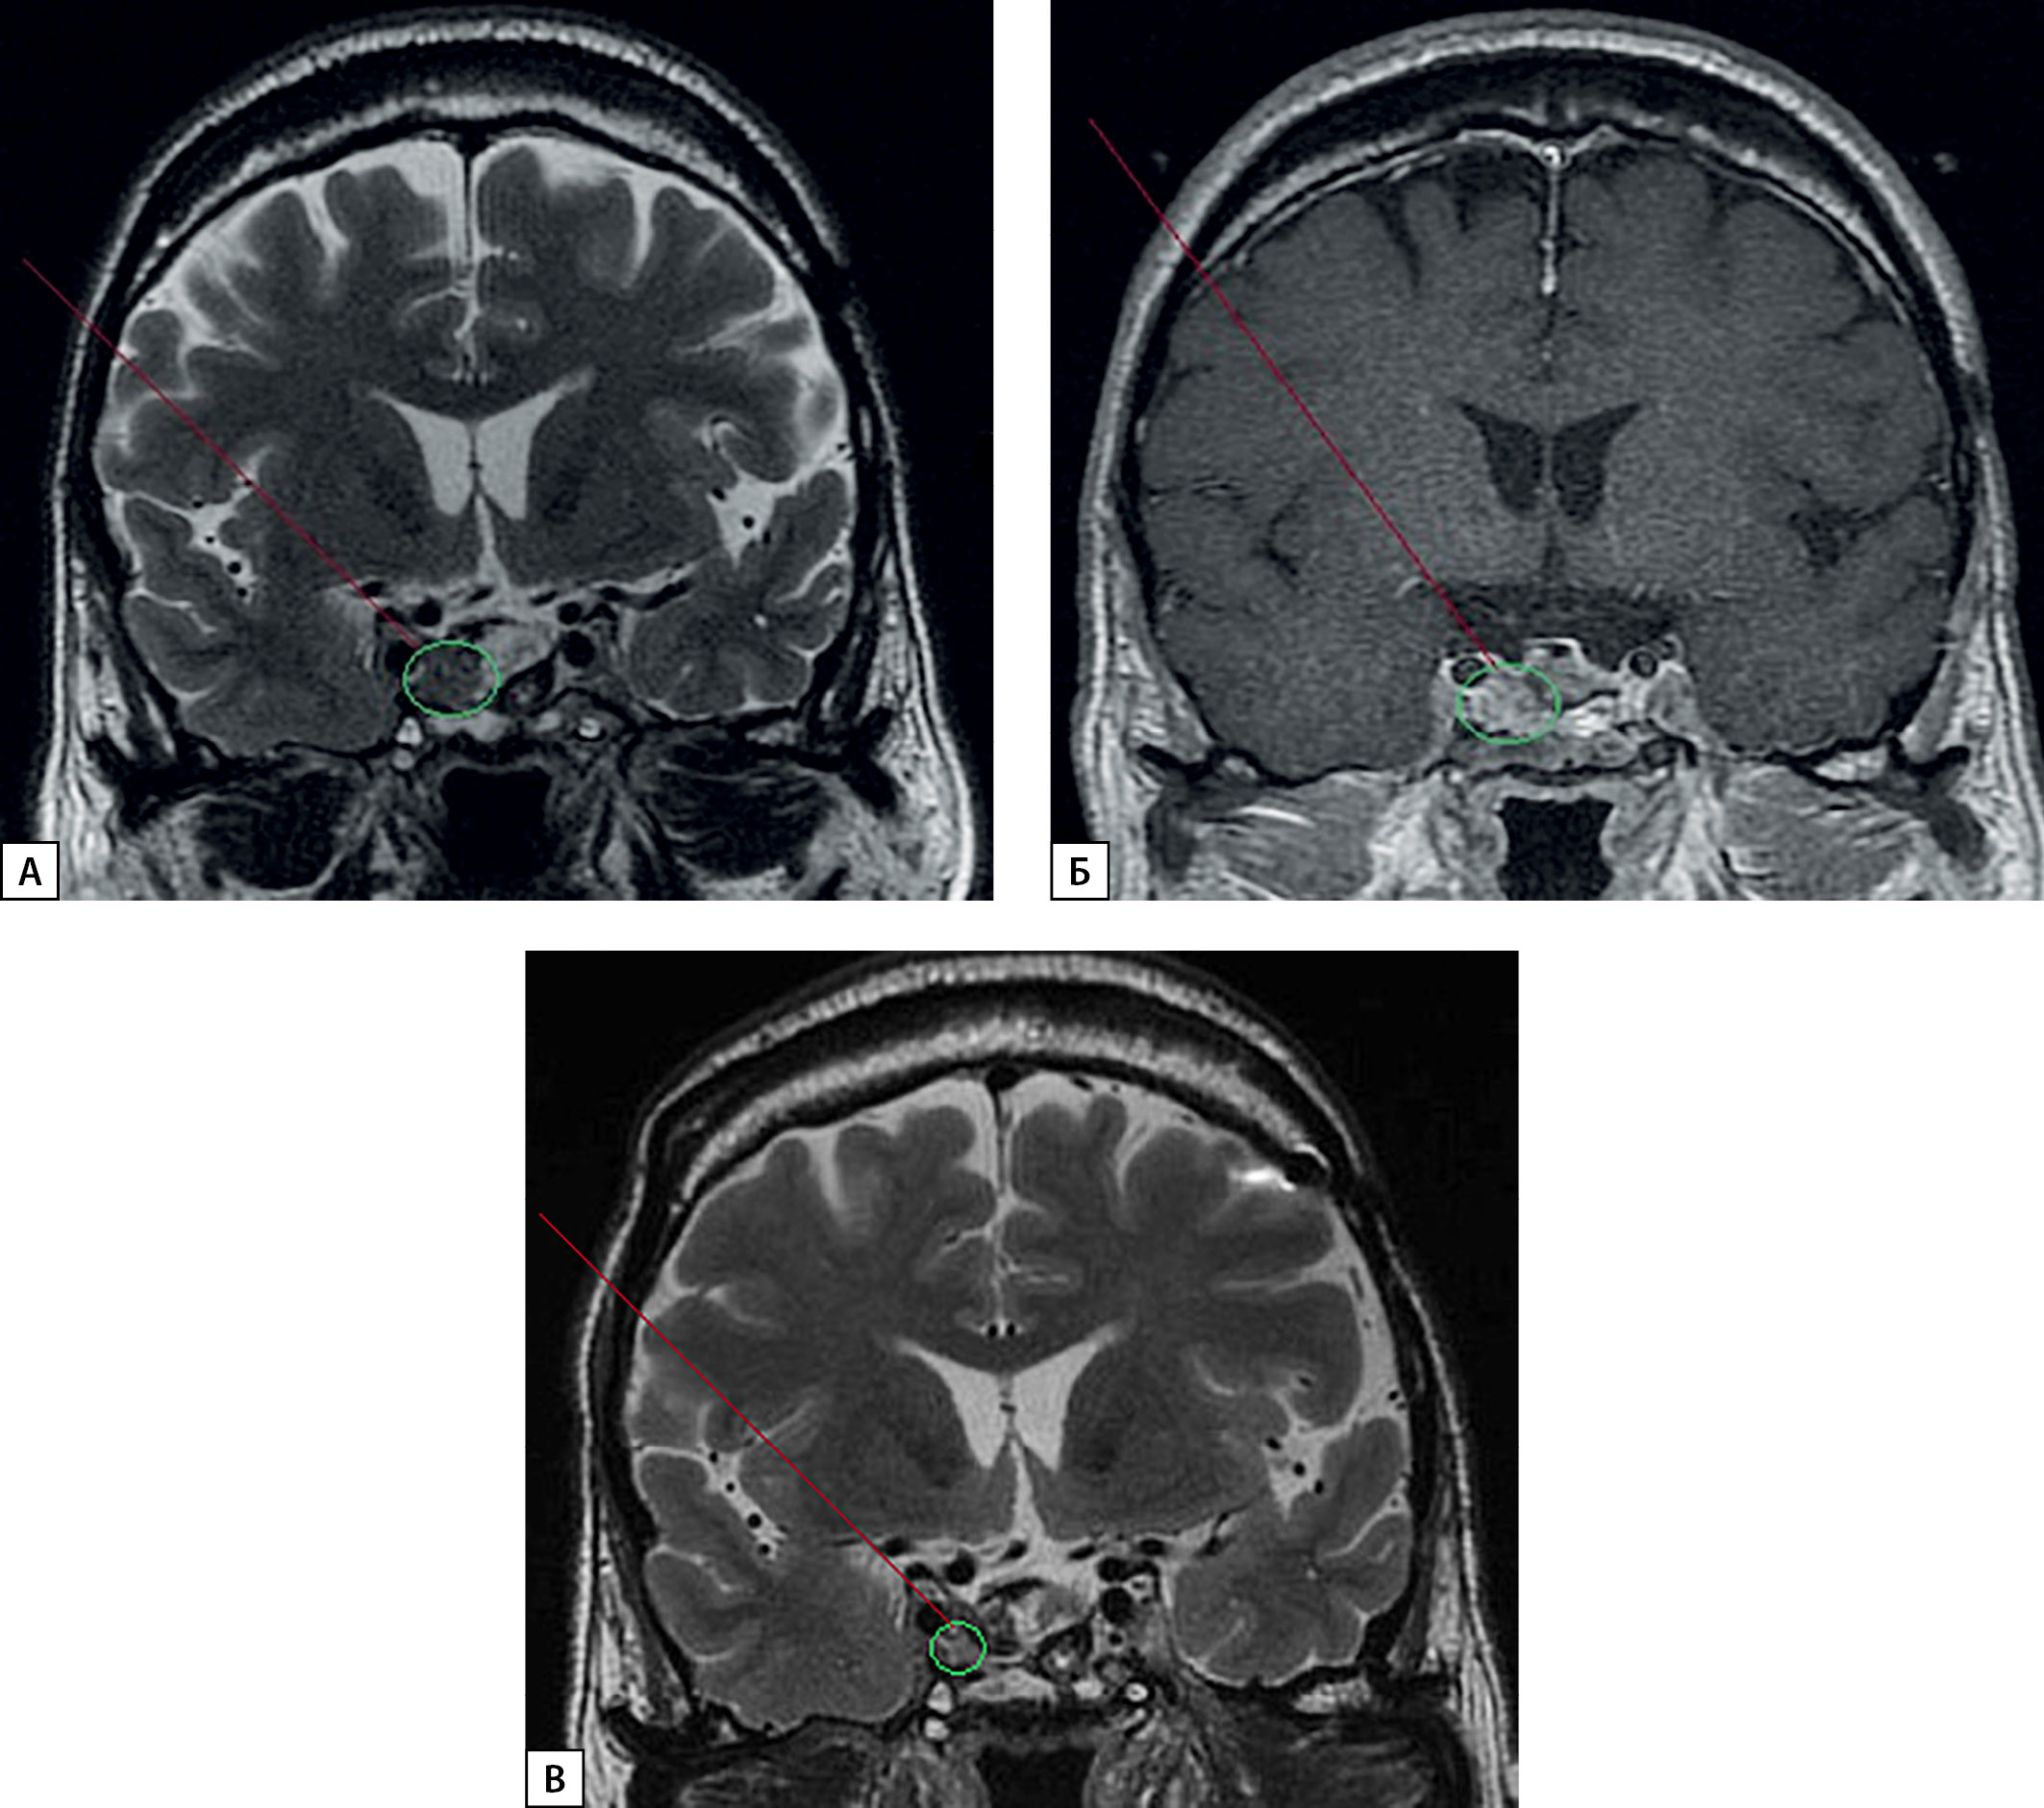

С января 2020 г. пациент стал отмечать выраженное ухудшение общего состояния в виде частой интенсивной головной боли, не купируемой приемом НПВС, прогрессирующего снижения остроты зрения, прибавки массы тела, декомпенсации сахарного диабета, требующей увеличения доз инсулина. По данным обследования: ИФР-1–332 нг/мл (выше нормы), гликированный гемоглобин — 8,4%, по МРТ гипофиза — остаточная ткань аденомы размерами 14×17×14 мм с параселлярным распространением вправо, Knosp IV) (рис. 2 А, Б). С учетом особенностей течения заболевания в ФГБУ «НМИЦ эндокринологии» Минздрава России принято решение о необходимости инициации терапии препаратом из группы антагонистов рецепторов гормона роста — пэгвисомантом (10 мг 1 р/сут п/к). Через 6 мес по данным контрольного обследования наблюдалась положительная клиническая и лабораторная динамика: уменьшение отечности мягких тканей, значительное снижение частоты и интенсивности головной боли, улучшение общего состояния, повышение чувствительности к инсулину, нормализация ИФР-1 — 162 нг/мл. В связи с отсутствием продолженного роста аденомы гипофиза с декабря 2020 г. терапия аналогами соматостатина отменена.

Рисунок 2. МРТ головного мозга пациента Ч.:

А — апрель 2020 г. (без контрастного усиления);

Б — апрель 2020 г. (с контрастным усилением);

В — ноябрь 2021 г. (без контрастного усиления).

Figure 2. MRI of the patient’s Ch. brain.

A — April 2020 (without contrast enhancement).

B — April 2020 (with contrast enhancement).

C — November 2021 (without contrast enhancement).

Последняя госпитализация больного в ФГБУ «НМИЦ эндокринологии» состоялась в ноябре 2021 г. (рис. 1Б, 2В). На фоне ежедневных инъекций пэгвисоманта (10 мг/сут) лабораторно подтверждена ремиссия акромегалии (ИФР-1 — 228,8 нг/мл, нормадо 245 нг/мл). При проведении МРТ гипофиза — остаточная ткань аденомы размерами 12×12×8 мм. Вторичная надпочечниковая недостаточность, вторичный гипотиреоз медикаментозно компенсированы. Наблюдается положительная динамика показателей углеводного обмена (гликированный гемоглобин — 7,4%). Субъективно пациент отмечает существенное улучшение самочувствия, позволяющее беспрепятственно продолжать привычный активный образ жизни.